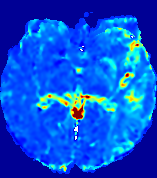

4.3.1 Advection Imaging via Advection-Diffusion

Slice #1Slice #2Slice #3Slice #4Slice #5Slice #6𝐕gt𝟐subscriptnormsuperscript𝐕gt2\|\bf{V}^{\text{gt}}\|_{2}Refer to captionRefer to captionRefer to captionRefer to captionRefer to captionRefer to caption𝐕est𝟐subscriptnormsuperscript𝐕est2\|\bf{V}^{\text{est}}\|_{2}Refer to captionRefer to captionRefer to captionRefer to captionRefer to captionRefer to captionRefer to caption1.51.51.51.21.21.20.90.90.90.60.60.60.30.30.30.00.00.0(mm/s)𝑚𝑚𝑠(mm/s)Destsuperscript𝐷estD^{\text{est}}Refer to captionRefer to captionRefer to captionRefer to captionRefer to captionRefer to captionRefer to caption0.0150.0150.0150.0120.0120.0120.0090.0090.0090.0060.0060.0060.0030.0030.0030.0000.0000.000(mm2/s)𝑚superscript𝑚2𝑠(mm^{2}/s)

Figure 14: PIANO identifiability testing: advection imaging via advection-diffusion. Top row shows 𝐕gt2subscriptnormsuperscript𝐕gt2\|{\bf{V}}^{\text{gt}}\|_{2} used for simulating ground truth pure advection. Rows below show the estimated 𝐕est2subscriptnormsuperscript𝐕est2\|{\bf{V}}^{\text{est}}\|_{2} and Destsuperscript𝐷estD^{\text{est}} on corresponding slices. Note that the plotted value scale for Destsuperscript𝐷estD^{\text{est}} is 0.01 of that for 𝐕gt2subscriptnormsuperscript𝐕gt2\|{\bf{V}}^{\text{gt}}\|_{2} and 𝐕est2subscriptnormsuperscript𝐕est2\|{\bf{V}}^{\text{est}}\|_{2}.

We use the same ‘Advection Imaging’ simulation of Sec. 4.2.1 as the concentration dataset for PIANO. However, instead of modeling pure advection (Eq. 15), we let PIANO estimate both velocity 𝐕estsuperscript𝐕est{\bf{V}}^{\text{est}} and diffusivity Destsuperscript𝐷estD^{\text{est}} via the advection-diffusion PDE (Eq. 2) underlying the proposed PIANO model. Fig. 14 shows the estimated 𝐕est2,subscriptnormsuperscript𝐕est2\|{\bf{V}}^{\text{est}}\|_{2}, and Destsuperscript𝐷estD^{\text{est}} fields for one patient. Although PIANO has the freedom to estimate both a velocity and a diffusivity field from pure advection, PIANO differentiates well between advection and diffusion: the estimated 𝐕est2subscriptnormsuperscript𝐕est2\|{\bf{V}}^{\text{est}}\|_{2} successfully reproduces the ground truth 𝐕gt2subscriptnormsuperscript𝐕gt2\|{\bf{V}}^{\text{gt}}\|_{2} governing the simulated advection process, just as it already did in the ‘Advection Imaging via Advection’ test (Fig. 12). More importantly, the estimated diffusivity Destsuperscript𝐷estD^{\text{est}} is orders of magnitudes smaller than 𝐕est2subscriptnormsuperscript𝐕est2\|{\bf{V}}^{\text{est}}\|_{2}, indicating the estimated diffusion is negligible compared to the estimated advection, which is highly consistent with the underlying pure advection of the simulated data.